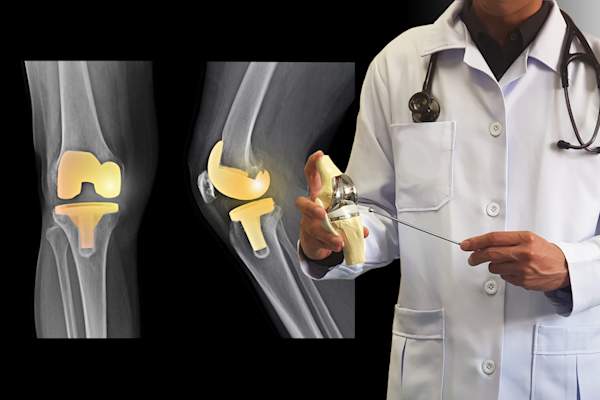

未来,手术可能是必要的

费利博士说,一旦非手术治疗方法用尽,关节置换手术可能是缓解疼痛的最佳选择。当受损的关节被移除并用金属或塑料部件替换,在骨头之间形成缓冲,这样它们就不会再摩擦。费利博士指出:“它不会让你恢复到没有受伤的状态。”但大多数患者对结果感到满意。费利博士说,年龄在55岁以下或极度活跃的患者可能需要接受另一种名为截骨术的手术,这种手术通过移除或增加骨头来调整臀部或膝盖的位置。